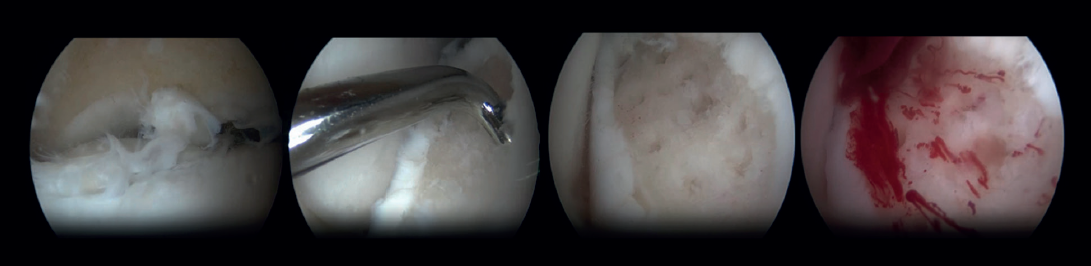

Arthroscopic Bone Marrow Stimulation (BMS) is the most frequently used treatment for primary OLT(22). BMS can be deployed for relatively smaller (<15 mm), non-cystic, non-fixable lesions(20,23). Arthroscopic BMS starts with debridement and curettage of the defective cartilage and subchondral bone(24). Subsequently, drilling or perforation of the sclerotic bone at the base of the defect is performed, often using a Kirschner wire or microfracture awl(25). The holes should be made to a depth that results in bleeding of the subchondral bone or the presence of fat droplets(23)(Figure 4). This technique disrupts the intraosseous blood vessels, leading to the subchondral bone bleeding and the formation of a fibrin clot. The release of mesenchymal blood cells promotes vascularization which induces the formation of fibrocartilage(26). When an isolated (i.e., no other damage to bone/within the joint) cartilage lesion with a macroscopically intact subchondral bone layer, is present, debridement only can be performed(27).

One specific surgical fixation technique is the Lift, Drill, Fill and Fix (LDFF) procedure(45). In this technique, the osteochondral lesion is visualized, and a beaver knife is used to create a flap. The flap is then lifted to allow for debridement and microfracturing of the subchondral bone. Cancellous bone, typically harvested from the distal tibial metaphysis, can be placed in the bed of the flap. Finally, the osteochondral flap is repositioned and fixed using bio-absorbable compression screws, chondral darts or bone pegs.